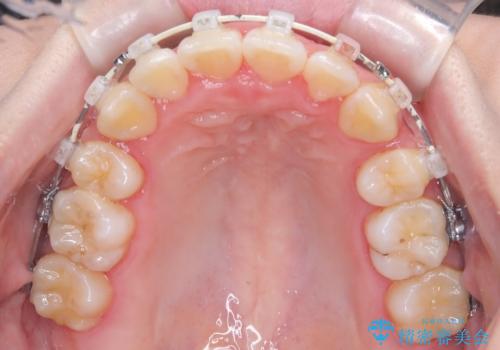

- 患者様は、結婚式までに歯並びを整えたいとのご要望で来院されました。診断の結果、上下左右の第一小臼歯を抜歯し、歯列全体を整える計画としました。審美性を重視し、目立ちにくいホワイトワイヤーを使用した矯正を提案しました。治療期間は2年を目安とし、結婚式までに前歯の整列と噛み合わせを優先的に整えるスケジュールで進めました。定期的な調整と経過観察を通じて、計画的に治療を進めました。

結婚式までに仕上げるため、通常よりも細かく調整を行い、歯の動きを効率的に管理しました。審美ワイヤーを使用したことで、治療中も目立ちにくく、写真撮影などの日常生活での見た目の負担を軽減しました。抜歯部分のスペースを閉じる際には、前歯の位置や噛み合わせのバランスに配慮し、過度な力がかからないよう進めました。患者様の大切なイベントに間に合うよう治療計画を立て、理想的な仕上がりを実現しました。